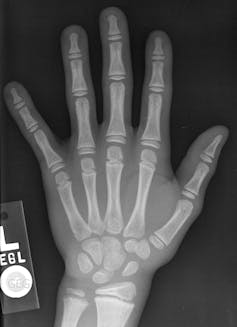

Quizá recuerde algún momento de la infancia en el que vio los huesos de su mano sobre un fondo oscuro. ¿Cómo era posible fotografiar algo que se escondía bajo la piel? ¿Qué tipo de truco usaba aquella persona que huía al otro lado del cristal durante un puñado de segundos?

La invención de la radiografía se la debemos al alemán Wilhelm Röntgen, quien a finales del s. XIX descubrió un nuevo tipo de rayos capaces de atravesar ciertos materiales. Como su naturaleza era desconocida, los llamó rayos X. Experimento va, experimento viene, observó que esa radiación podía atravesar el tejido humano con más facilidad que los huesos. Así logró la primera radiografía médica de la historia, la de la mano de su mujer, Bertha.

Ha pasado más de un siglo desde aquel momento y, pese a que se han realizado numerosos avances, el fundamento sigue siendo básicamente el mismo. Para comenzar se necesita una fuente que emita rayos X, un tipo de radiación de la misma naturaleza que la luz visible, pero más energética y con mayor capacidad de penetración.

| Radiografía de una mano de un niño de 8 años. Bonepit.com / Wikimedia Common |

Los rayos X atraviesan en mayor o menor medida el objeto que se ponga en su camino y llegan a una placa fotográfica. Esta placa está formada por ciertos compuestos químicos (haluros de plata) que, al entrar en contacto con los rayos X, se oscurecen. Por lo tanto, cuantos más rayos X incidan sobre una zona, más se oscurecerá ésta.

Dado que los rayos X atraviesan con más facilidad los materiales con átomos más ligeros, como los que hay en la piel y los músculos, estas partes del cuerpo se verán más oscuras en la radiografía. Todo lo contrario pasa con los huesos que, al estar formados por átomos más pesados, aparecen más blancos. Obviamente, el grado en el que se oscurece la placa también depende de la densidad o el grosor del objeto: cuanto mayor sea, menos rayos conseguirán atravesarlo y más clara será la radiografía.